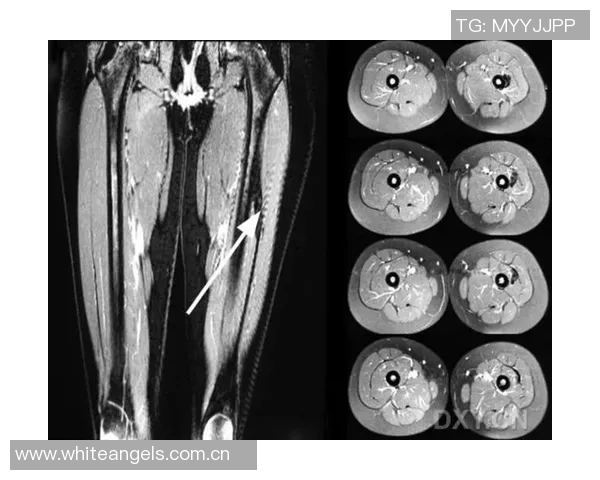

为了进一步确认诊断,医生建议进行了影像学检查,包括MRI扫描。结果显示右大腿后群肌纤维部分撕裂,同时伴随周围组织水肿现象。这种情况符合I级肌筋膜炎,即轻度损伤,但仍需认真对待,以免延误康复过程。

综合以上症状及检查结果,可以确诊为右大腿后群肌肉拉伤及肌筋膜炎I级。对此,需要制定科学合理的治疗方案,以帮助李磊早日恢复正常运动功能。